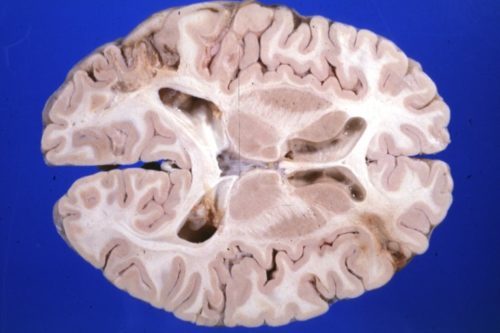

Сосудистые мальформации головного мозга

Последствиями патологии являются разрывы сосудистой стенки с кровоизлияниями, ишемия, аневризмы. Лечение только хирургическое, направленное на удаление, эмболизацию или облитерацию мальформации. Что это такое В норме